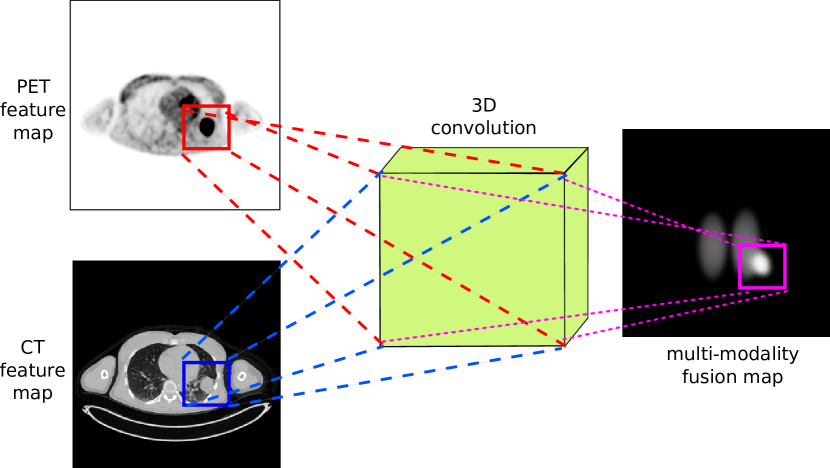

II-D Multi-modality Feature Co-Learning and Fusion

The co-learning component consists of two parts: (i) a co-learning unit that is a CNN that learns to derive spatially varying fusion maps, and a (ii) fusion operation that uses the fusion maps to prioritize different features. Fig. 2 shows a conceptual example of the function of the multi-modality co-learning unit. The inputs to the co-learning unit are two feature maps and (each from a block of one modality-specific encoder), each of size with width, height, and channels. These feature maps are stacked to form , a tensor with number of modalities. The channels of are then convolved with the channels of a learnable 3D kernel of size , where is the width and height of the kernel, and is the number of modalities.

By performing a 3D convolution [67] without padding the modality dimension, we obtain for a given channel a feature map with a singleton third dimension where the value at location is determined from the neighborhood of both and :

| (2) |

We then squeeze the singleton third dimension to obtain an output feature map of size , the same width and height as the two modality-specific input feature maps and and double the number of channels, which is important for the weighting of modality-specific feature maps by the co-learned fusion maps as described below.

Our intention is that the co-learned fusion map controls the level of importance given to information from each modality at each location, in contrast to the global fusion ratio in PET-CT pixel intermixing [68, 69, 70]. Thus the co-learned fusion maps directly affect the input distribution of the learnable layers that immediately follow the co-learning unit. Hence, we do not normalize the output of the 3D convolution within the co-learning unit. As with the encoders (see Section II-C), we used a Leaky ReLU activation function to obtain the multi-modality co-learned fusion map:

| (3) |

where are the learned biases. Note that the multi-modality fusion map is obtained by the co-learning unit based on the spatial integration of the features from both modalities, since the 3D convolution operation considers the 3D neighborhood defined by the width, height, and modality of the stacked feature map .